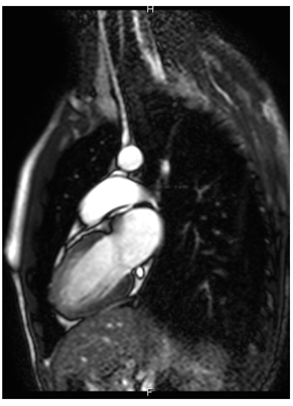

The patient was then taken for a cardiac magnetic resonance imaging exam which revealed an ejection fraction of 60%, delayed enhancement involving the mid lateral wall, a portion of the inferior wall, and a portion of the epicardial wall in the inferolateral area, consistent with focal myocarditis in the inferolateral wall (Figure 2a), (white arrow).

Figure 2A Cardiac magnetic resonance imaging exam which revealed an ejection fraction of 60%, delayed enhancement involving the mid lateral wall, a portion of the inferior wall, and a portion of the epicardial wall in the inferolateral area, consistent with focal myocarditis in the inferolateral wall(white arrow).